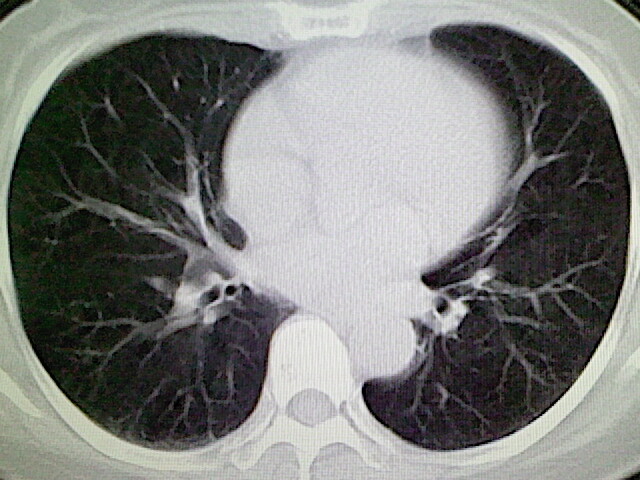

女,52岁,咳嗽,咳痰多日

左下肺陈旧纤维索条!

左肺舌段炎性改变

我见过几例,为炎症后纤维条索

慢性炎症后改变

考虑慢性炎性病灶粘连牵拉改变。

左肺舌叶纤维锁条病变。

左肺上叶下舌段炎症并局部胸膜反应。

左肺舌叶纤维索条影。

左肺舌叶段陈旧性病变

左肺舌段炎性反应。片子的质量太不好了。

左肺舌段炎性

炎性改变

左肺舌叶纤维索条影